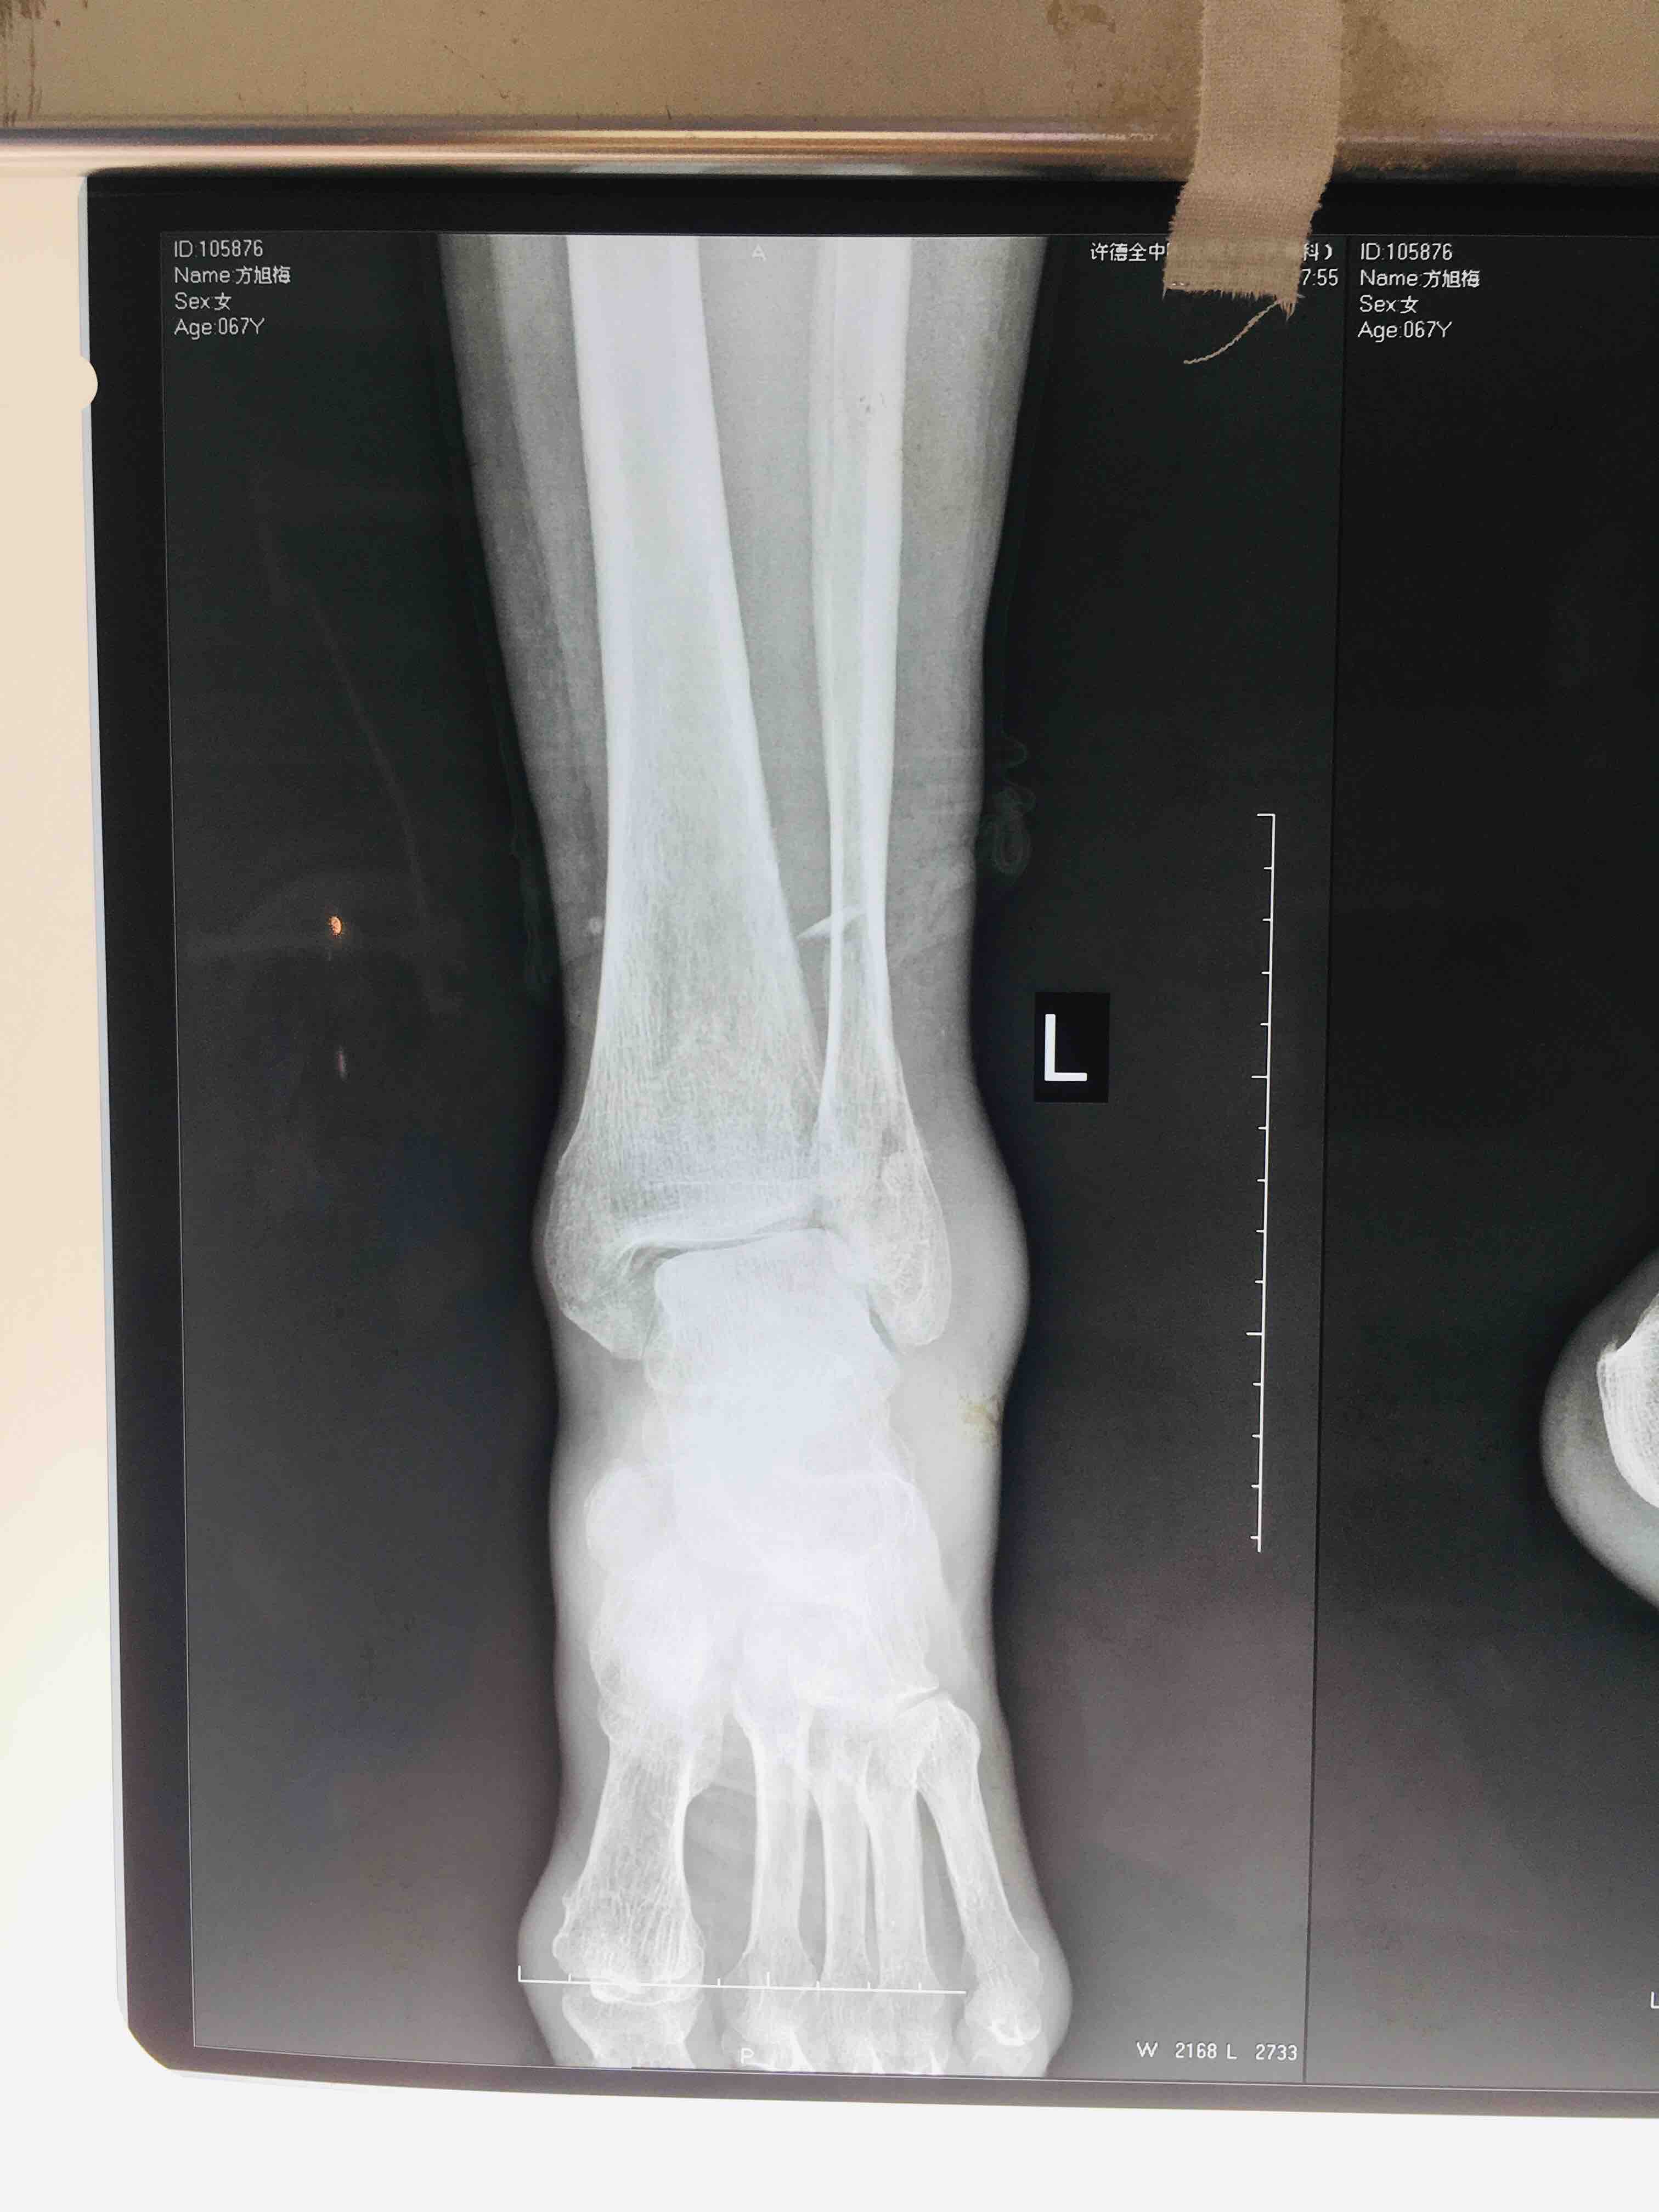

三踝粉碎性骨折(切复内固定术)

摔伤后左踝肿胀,疼痛,活动受限1小时入院。既往身体状况一般。无特殊不良癖好。

生命体征平稳,心肺复未见异常。左踝肿胀明显,畸形,局部皮色发红,皮温高,压痛及纵向叩击痛阳性,末梢血运感觉正常。

急诊行骨牵引,消肿等处理,在腰麻下行切复内固定术,术后抗炎,消肿。